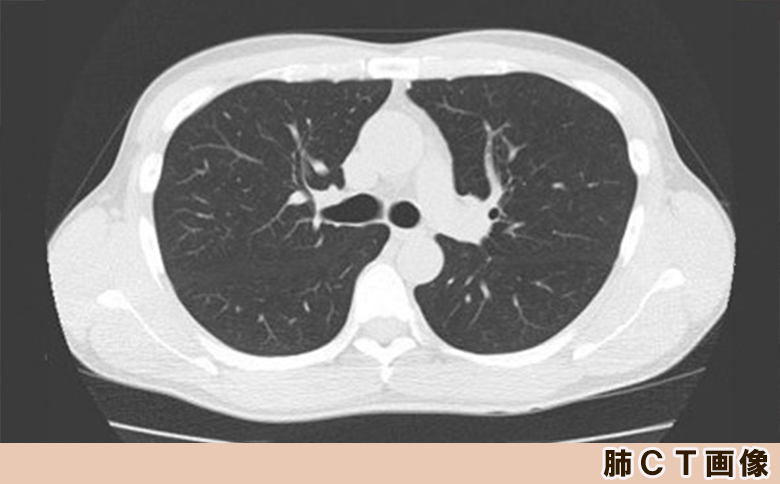

CTを使用した、詳しいレントゲン検査です。

体の中を断層したような画像で診断が可能です。胸部X線検査よりも詳細に体内を観察する事ができ、肺がんの発見精度が数段高くなります。